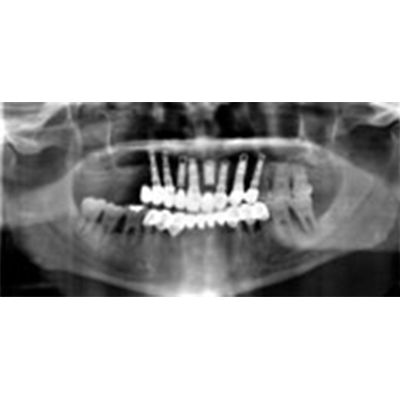

Additional procedures

Prior to implant surgery, it is important to be evaluated by an oral surgeon. A full mouth x-ray, or a panorex, will be taken and an exam performed to determine the amount of bone available and the position of the sinuses and the inferior alveolar nerve, which gives feeling to the lower lip and chin. There are often situations in which additional procedures are necessary to prepare a patient for implant surgery. The most common of these procedures include bone grafting, sinus lifts, and nerve repositioning.